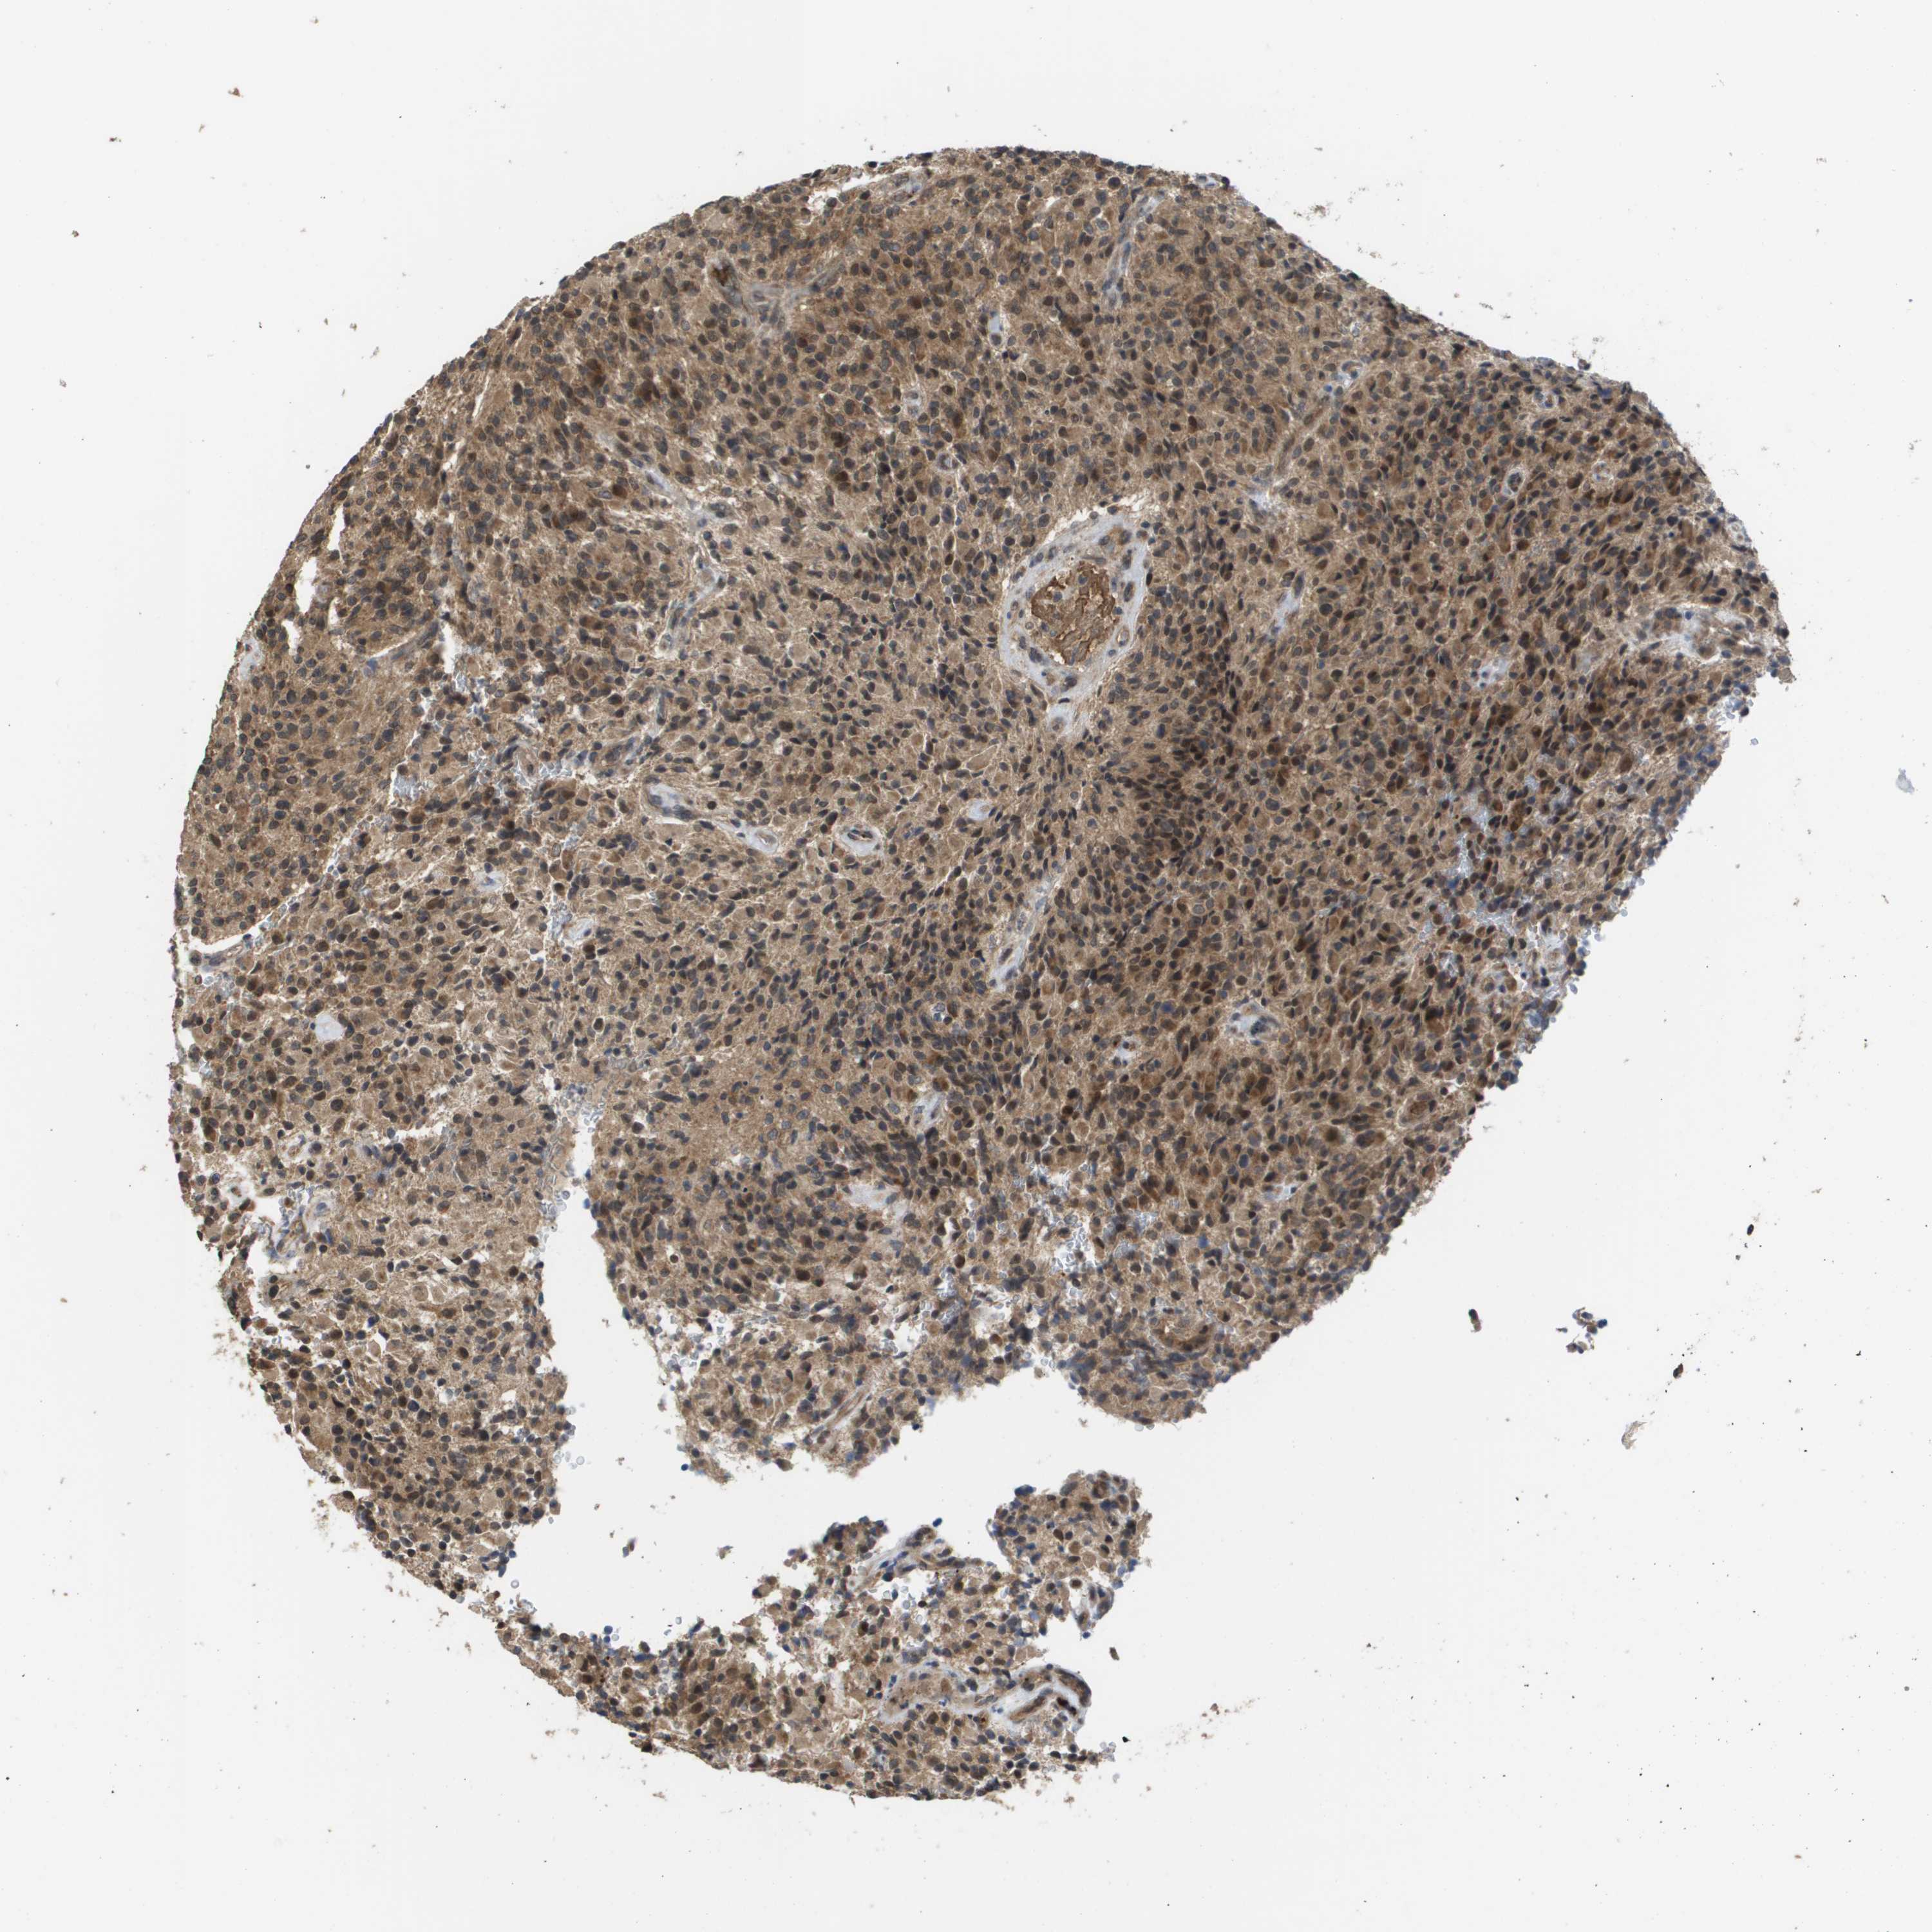

GLIOMA - Protein expressioni

A mouse-over function shows sample information and annotation data. Click on an image to view it in a full screen mode. Samples can be filtered based on level of antibody staining by selecting one or several of the following categories: high, medium, low and not detected. The assay and annotation is described here.

Note that samples used for immunohistochemistry by the Human Protein Atlas do not correspond to samples in the TCGA dataset.

Antibody stainingi

Antibody staining in the annotated cell types in the current human tissue is reported as not detected, low, medium, or high, based on conventional immunohistochemistry profiling in selected tissues. This score is based on the combination of the staining intensity and fraction of stained cells.

Each image is clickable and will lead to virtual microscopy that enables deeper exploration of all samples and also displays staining intensity scores, fraction scores and subcellular localization as well as patient and tissue information for each sample.

Antibody CAB017036

Staining

High

Medium

Low

Not detected

Intensity

Strong

Moderate

Weak

Negative

Quantity

>75%

75%-25%

<25%

None

Location

Nuclear

Cytoplasmic/membranous

Cytoplasmic/membranous,nuclear

Glioma, malignant, High grade

Glioma, malignant, Low grade